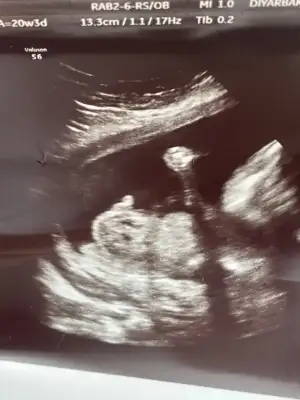

Kızlar bizede 20.haftaya kadar net kız dendi yavrumun genital organını gösterdiler en son bu hafta baktı pipi gibi çıkıntı gördü 3 doktora gittik hepsi belirsiz dedi ambigus genitalya tanısı dediler yıkıldık hemen amniyosemtez yaptık bekliyorum bu da en son ultrason resimleri